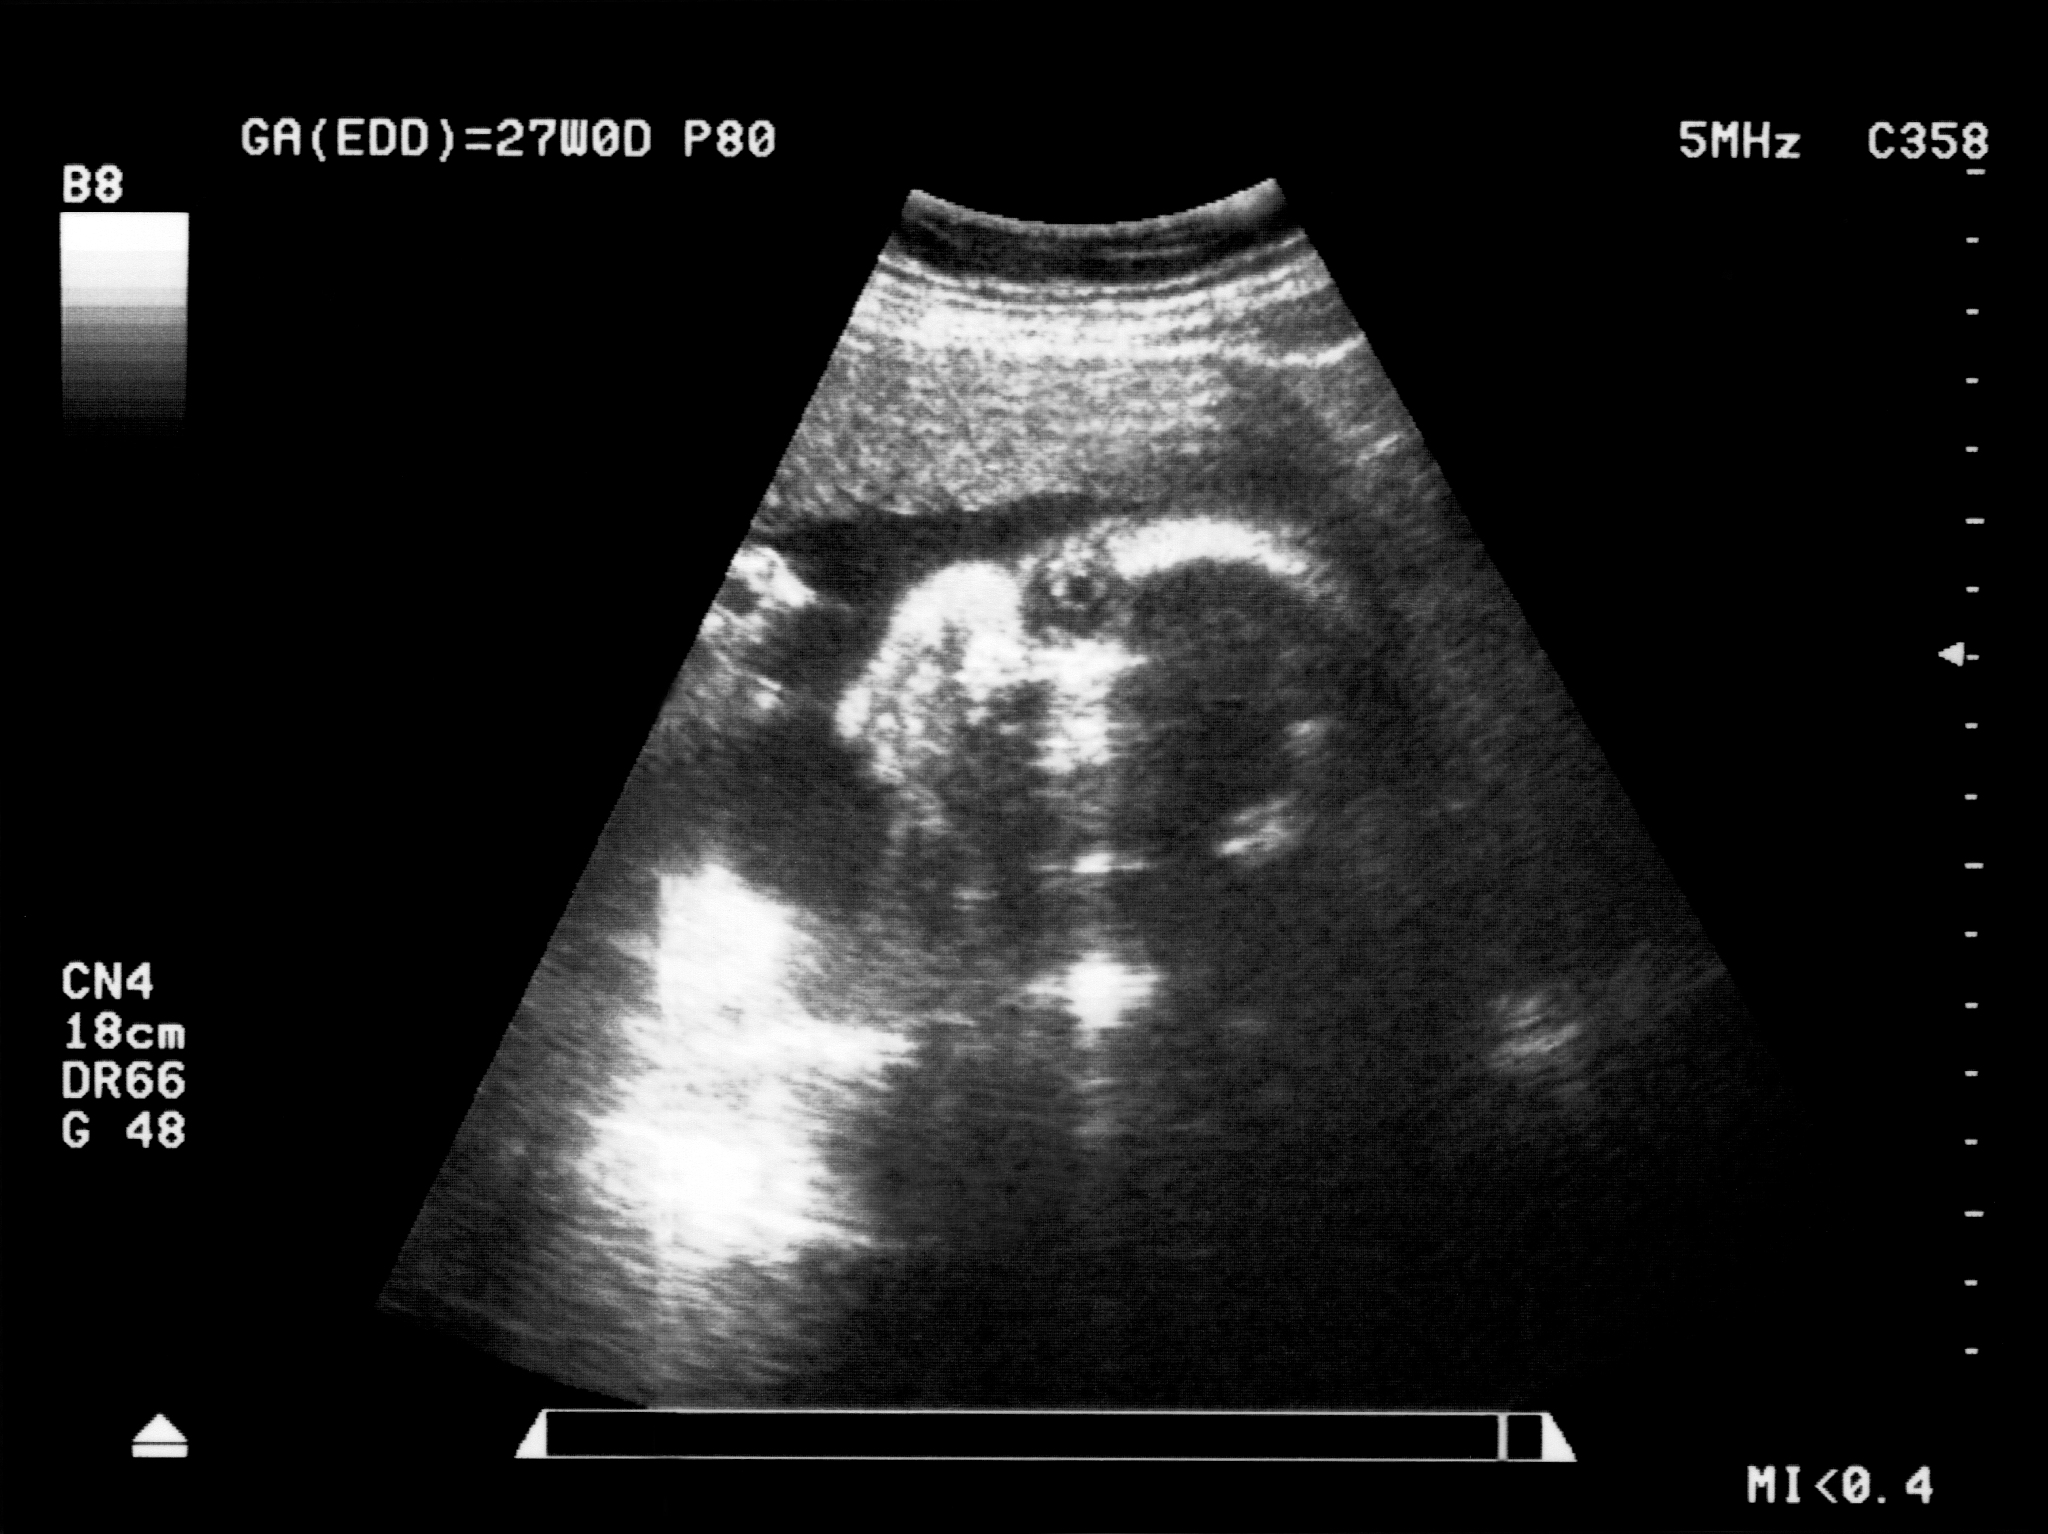

2. 声动奇迹:超声科作为一门技术和学科,通过声波的传导和成像,可以实现对人体内部的准确观察和诊断。"声动奇迹"暗示着超声科的技术和医疗手段能够创造奇迹,帮助患者获得准确的诊断和有效的治疗。